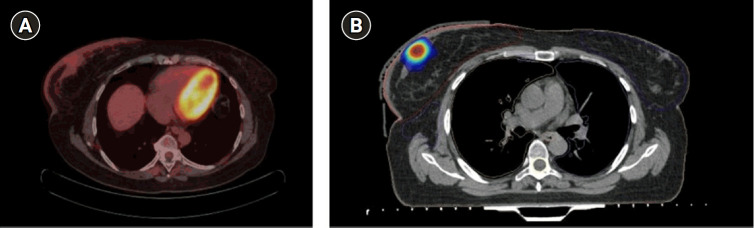

Inflammatory breast cancer (IBC) is a rare, aggressive form of breast cancer characterized by poor prognosis. The treatment requires a multidisciplinary approach, with neoadjuvant chemotherapy, surgery, and radiation therapy (RT). Particularly, high doses of conventional RT have been historically delivered in the adjuvant setting after chemotherapy and mastectomy or as radical treatment in patients ineligible for surgery. Here, we report the case of a 49-year-old woman patient with IBC unsuitable for surgery and treated with a combination of lattice RT and fractionated external beam RT concurrent with trastuzumab, with a curative aim. One year after RT, the patient showed a complete response and tolerable toxicities. This is the first reported case of a not-operable IBC patient treated with this particular kind of RT.